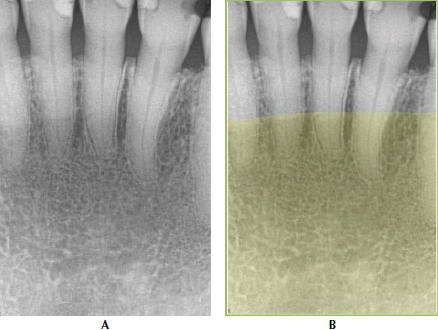

63. What arrow shows?

Nasolabial Fold An oblique line demarcating a region that appears to be covered by a veil of slight radiopacity frequently traverses periapical radiographs of the premolar region. The line of contrast is sharp, and the area of increased radiopacity is posterior to the line.